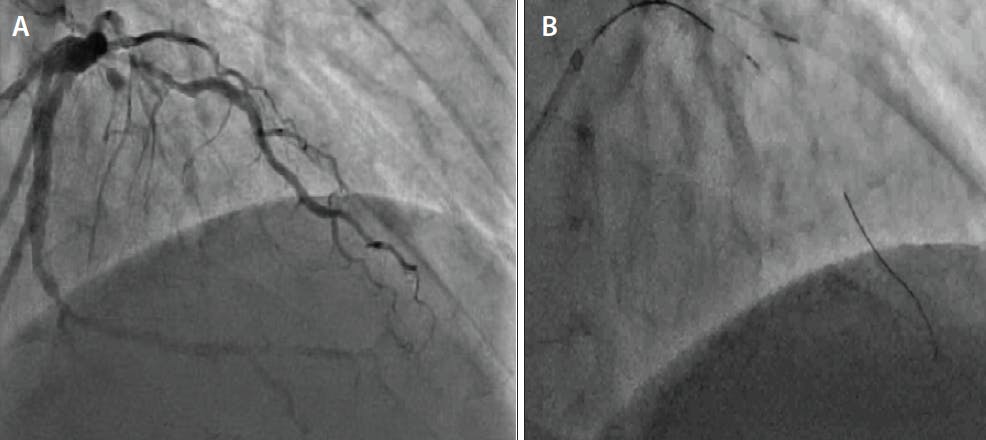

Figure 1. Pre-PCI angiography demonstrates bifurcation CTO disease involving a large first diagonal artery with proximal stenosis and mid left anterior descending (LAD) artery CTO with left-to-left, septal-to-septal, and diagonal-to-diagonal collaterals (Video 1) (A). The CTO was crossed with antegrade dissection reentry into the second diagonal. In this still frame, there is a wire positioned in the distal second diagonal. A microcatheter is positioned in the first diagonal that was used for visualization of collaterals to the LAD artery and second diagonal. The second diagonal takeoff was near the distal CTO cap. A Sasuke DLM with the OTW port was positioned at the CTO distal cap to access the LAD (B).

Figure 2. Still frame depicting successful wiring of a LAD artery CTO using the Sasuke DLM (A). Final results after successful CTO intervention with bifurcation stenting to the LAD and diagonal (Video 2) (B).